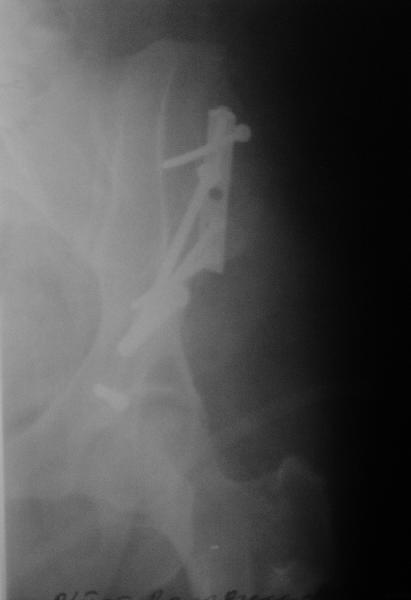

Выполнена реконструкция крыла левой подвздошной кости, грыжесечение через подвздошно-бедренный доступ. 2 фрагмента подвздошной кости, грыжа выходит между ними (см. картинки). Грыжевой мешок, спаянный с ПЖК, подвздошной костью, вскрыт, его содержимое (петли кишечника) вправлено в брюшную полость. Грыжевой мешок выделен, иссечен, наложены два ряда отдельных швов на брюшину. Отломки подвздошной кости стянуты друг с другом, зафиксированы 1/3-трубчатой пластиной и винтами к телу подвздошной кости (см. рентгенограммы). Дефект подвздошной кости был закрыт практически полностью. Решено не применять сетку. Иссечен лоскут истонченной кожи 15 на 8 см.